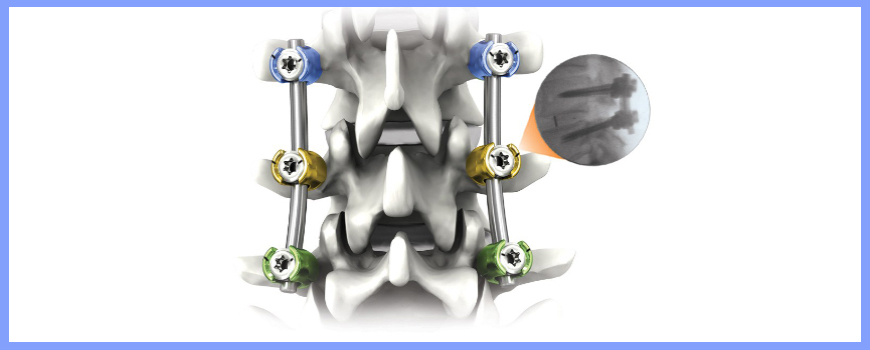

These fractures can be treated very well with the help of Pedicular screw system. This system and the C arm image intensifier equipment are very useful to correct and fix these vertebral fractures in the best possible position. After the spinal fixation, it is possible for the patients to sit and walk very early and the fixation gives very good pain relief.